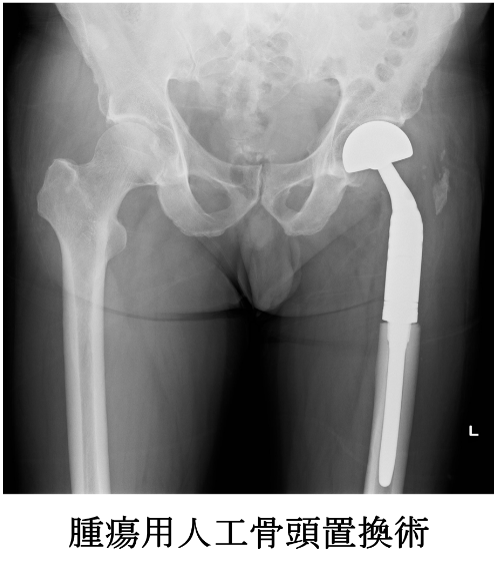

腫瘍用人工骨頭置換術

当科では、大腿骨近位部の骨腫瘍、特に転移性骨腫瘍に対して腫瘍用人工骨頭置換術を数多く行っております。骨接合術と比較して術後の歩行訓練を早期から行うことができる利点があり、術後の歩行機能も良好です。主に使用しているのはKyocera社のKMLS systemです。幅広いバリエーションが選択できるモジュラータイプのインプラントで、ステムの固定法もセメント固定とセメントレス固定が選べる仕様となっております。